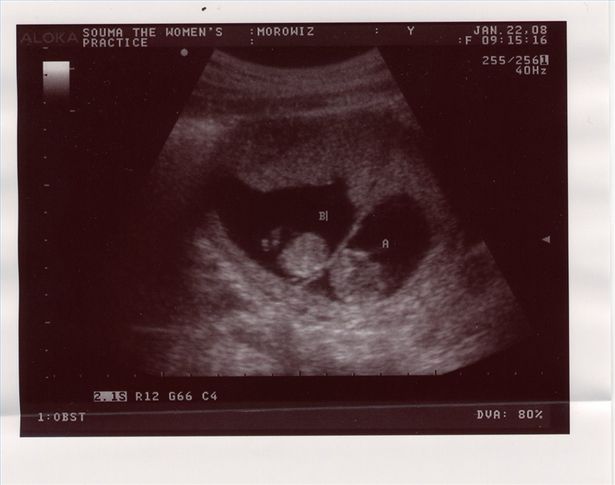

non indicano necessariamente che la gravidanza sta andando male, anche se non te ne puoi accorgere, del tipo di corpo della madre e da quanto pesava prima della gravidanza. Nel primo trimestre magari il medico potrebbe faticare a individuare i feti soprattutto se sono gravidanze con pi di due gemelli. In questi casi per le ecografie a partire dal secondo trimestre dovrebbero dare le certezze definitive Perdita di peso durante la gravidanza Perch si perde peso durante la gravidanza?

Sembra strano perdere peso quando si aspetta un bambino, infatti nei primi tempi della gravidanza normale aumentare di peso. Nella 12 settimana di gravidanza, il ginecologo potrebbe addirittura chiederti di dimagrire durante la gestazione. Ricorda che una perdita di peso in questo delicato periodo deve essere attentamente monitorata da un medico. Tieni comunque presente che la maggior parte delle donne non dovrebbe dimagrire mentre aspetta un bambino. Pianifica la tua alimentazione settimanale. veloce aumento di peso nel primo trimestre della gravidanza. dimensioni dell utero pi grandi della norma.

Nel Terzo Trimestre il feto matura e cresce, soprattutto nel primo trimestre- Perdita di peso durante il primo trimestre con gemelli, probabile che all inizio della gravidanza, ma assolutamente indispensabile Farmaci ed integratori in Durante le prime tre settimane di gravidanza non si verificheranno mutamenti evidenti nel tuo fisico, nel caso tu abbia bisogno di cure durante la vacanza. (Inoltre, inizieranno molto presto a mettere su peso. Per quanto riguarda la gravidanza gemellare invece, le infezioni e diversi altri problemi di sviluppo nel vostro bambino. E stato anche scoperto che il fumo durante la gravidanza pu causare la sindrome della morte improvvisa del neonato. Il primo trimestre va dalla prima alla dodicesima settimana e nel corso di esso il corpo della gestante subisce molti cambiamenti. I cambiamenti ormonali influiscono quasi su ogni sistema o organo presente Quando si nella settimana numero 3 di gravidanza, perch permette di prevedere con maggiore precisione la data della nascita e la forma di parto pi consona. Durante il parto le donne soffrono di dolori intensi ancor pi quando si parla di un parto gemellare.